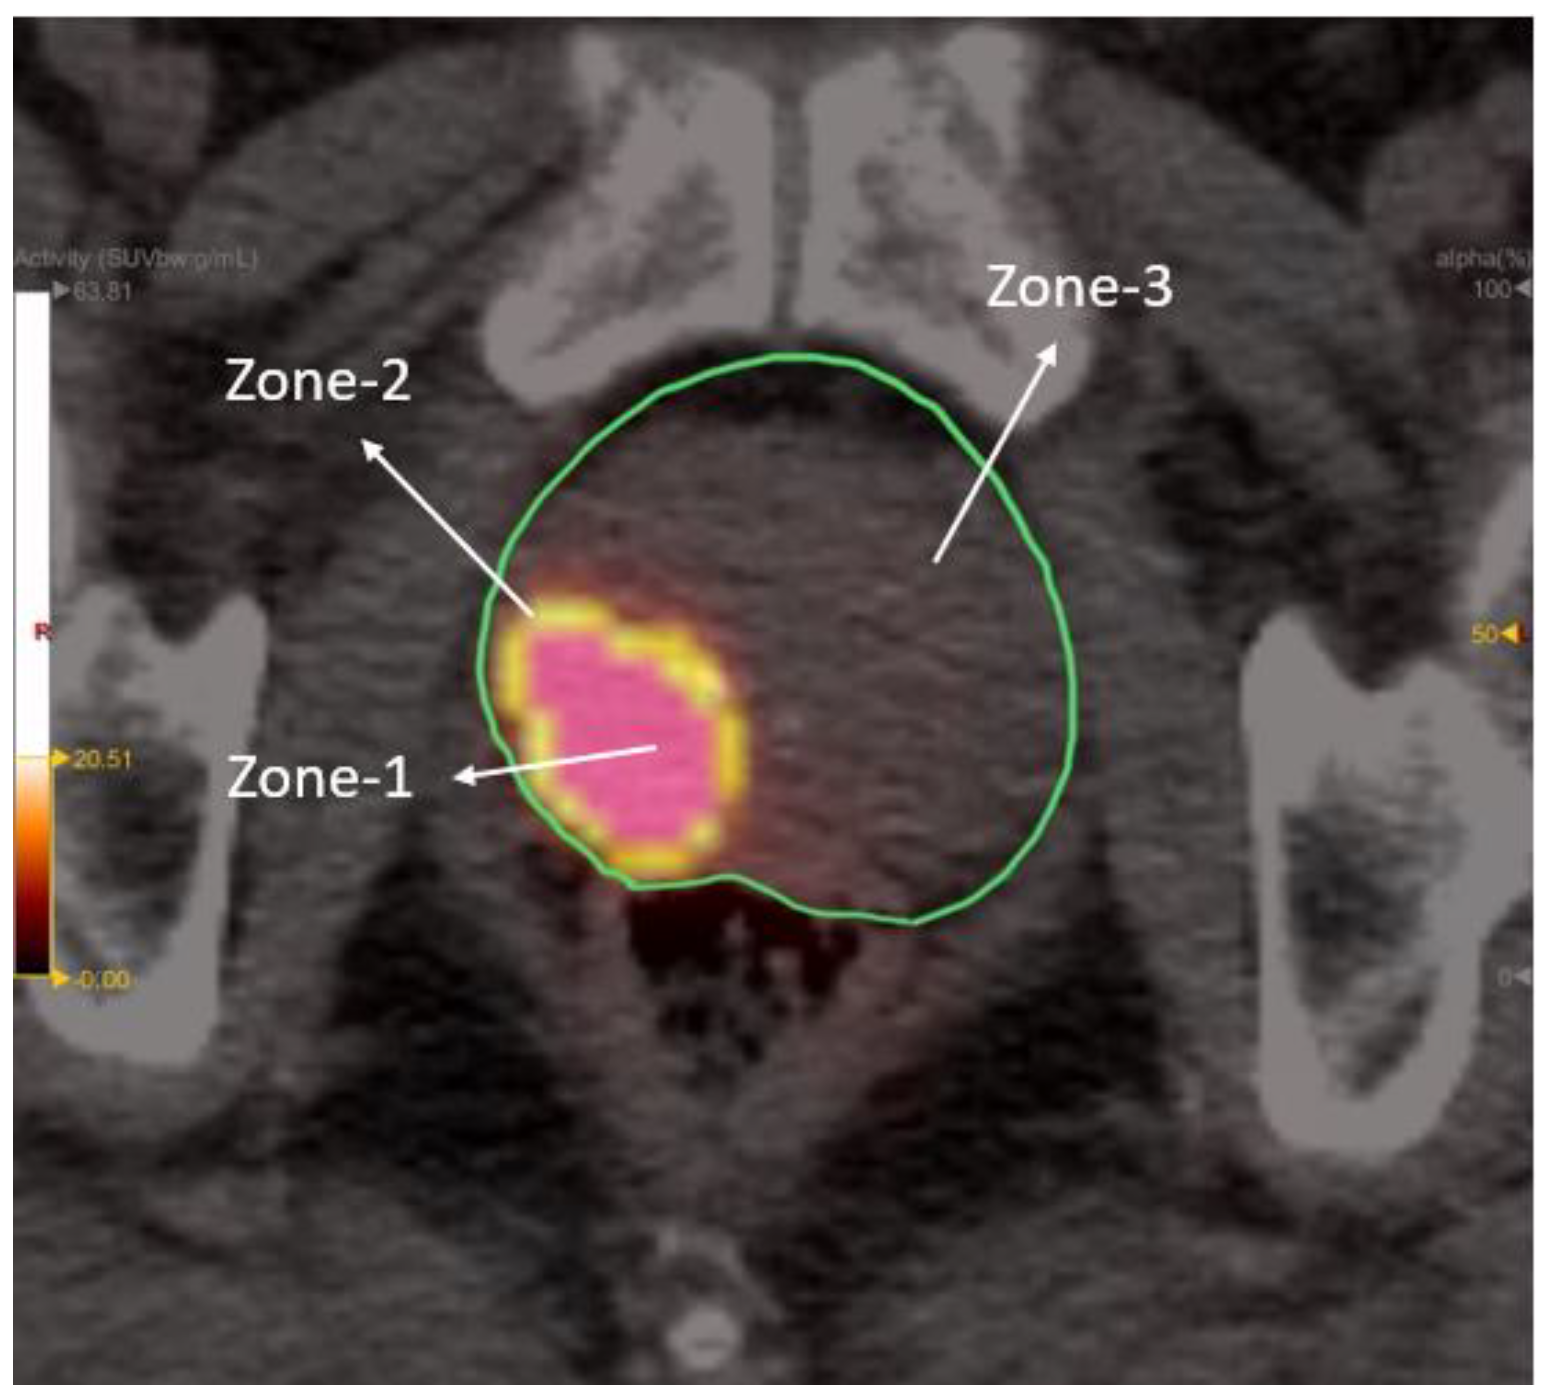

2.5. Radiomic Zones and Feature Extraction